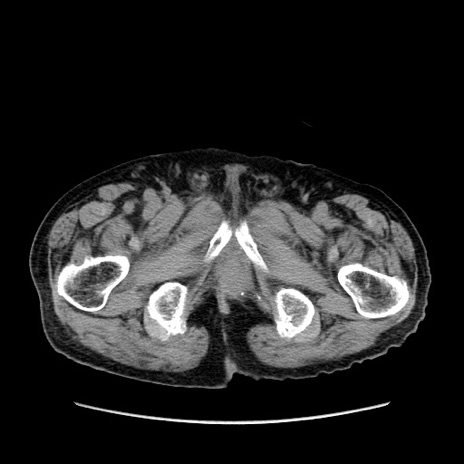

症例24(横断像)

【症例】80歳代男性

【主訴】左側腹部痛、嘔吐

【現病歴】本日早朝より左腹部に痛みあり。昼頃嘔吐認めたため、救急要請。

【既往歴】直腸癌(Mile手術)、胆摘

【身体所見】意識清明、BT 35.9℃、BP 221/93mmHg、SpO2 97%(RA) 、腹部:左ストーマ周囲に限局性の腹部膨隆あり。 膨隆部自発痛・圧痛あり・軟。

【データ】WBC 7700、CRP 0.09